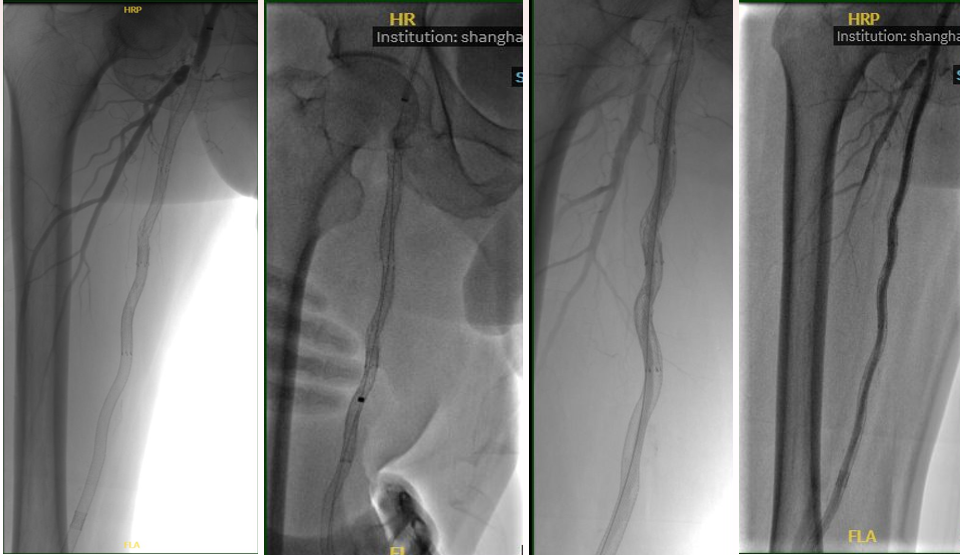

★ 病例基本情况

84岁女性患者,因"右足背、拇趾溃疡半年,支架植入术后4年余"就诊。患者4年前因下肢缺血行支架植入术,近期症状复发加重。

图:术前CT

★ 术前评估

血管造影显示股腘动脉长段支架内再狭窄,伴有严重钙化。

★ 术中造影

图:术中造影